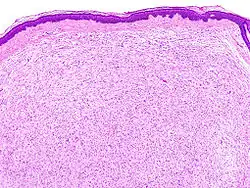

Obraz histologiczny

Mikroskopowo nerwiakowłókniak składa się ze składników obwodowych pni nerwowych: neurytów, komórek Schwanna, fibroblastów oraz śluzowatego i zdezorganizowanego podścieliska.